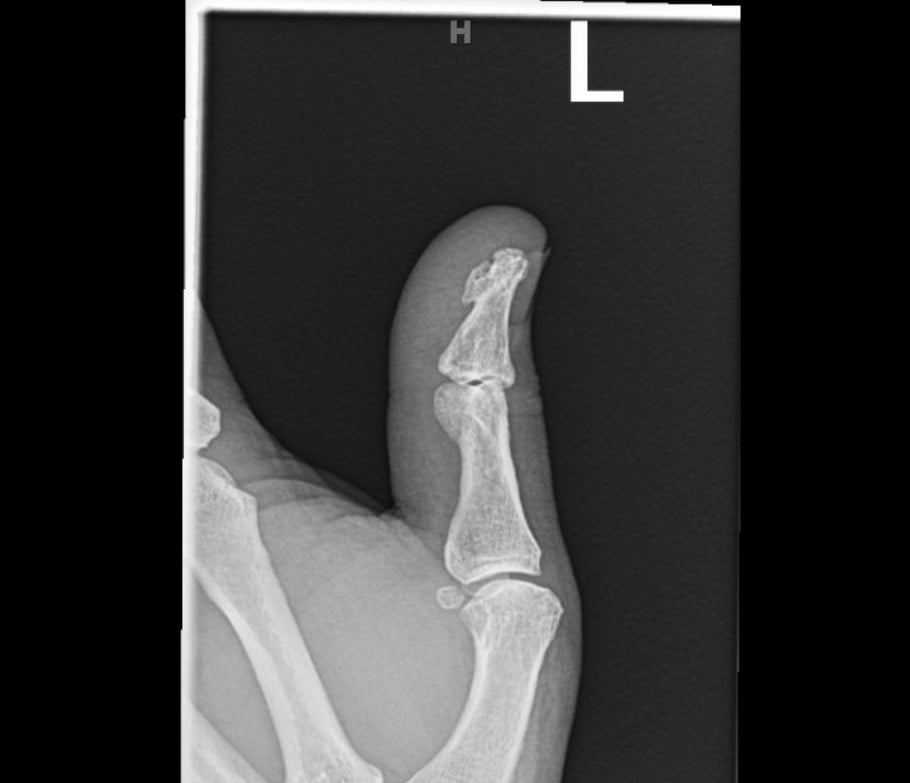

Post-foreign body removal with cast application X-rays were obtained which redemonstrated the vertically oriented, longitudinal fracture of the left thumb proximal phalanx extending into the interphalangeal joint. Removal of the foreign metal nail also allowed for appreciation of an intra-articular fracture at the distal ulnar aspect of the proximal phalanx where the metallic nail had been previously located, and a distal phalanx base fracture as well. No retained metallic foreign bodies were identified. Of note, there was no involvement of the metacarpal phalangeal joint of the thumb, making this an isolated injury involving only a single joint of the thumb.